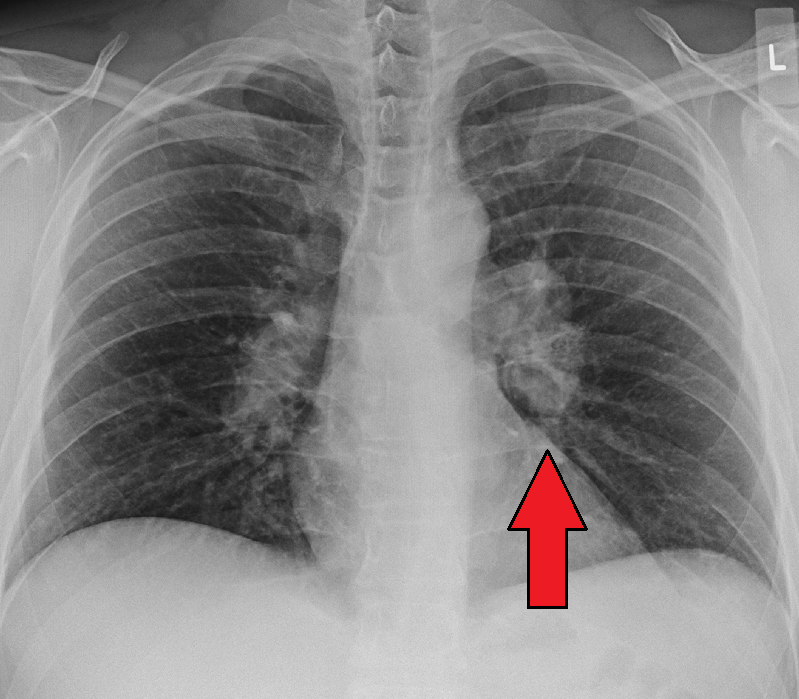

Fibrosis on lung CT shows subpleural patches, which progress to diffuse fibrosis and eventually forms a ‘honeycomb’ pattern which is an indicator of end-stage pulmonary fibrosis.